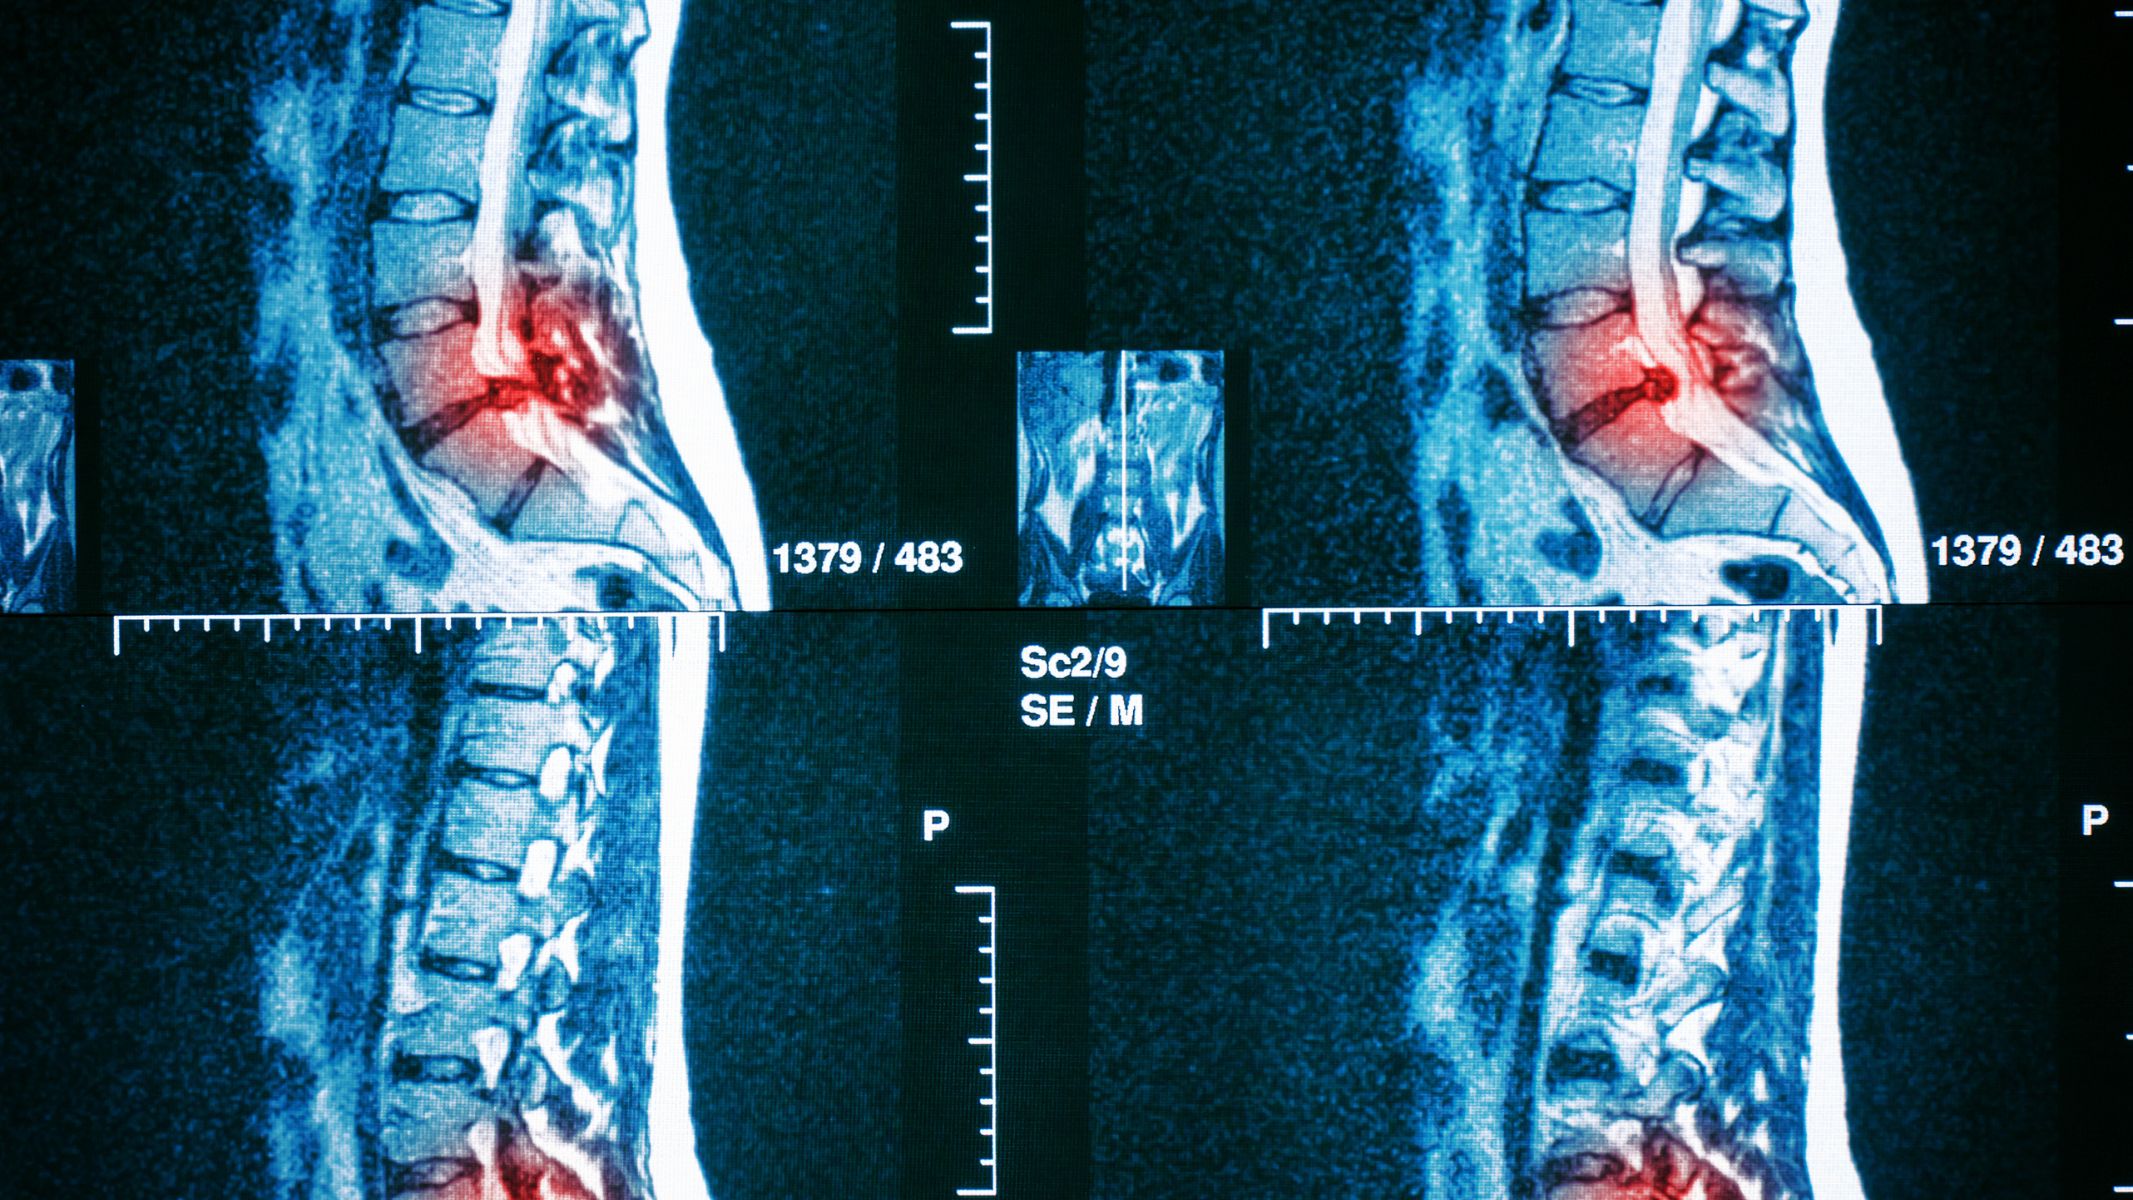

MRI đặc biệt hữu ích trong việc phát hiện và đánh giá các bệnh lý như thoát vị đĩa đệm, thoái hóa cột sống, hẹp ống sống hoặc tổn thương tủy sống. Đây là những bệnh lý mà các phương pháp chẩn đoán hình ảnh thông thường khó đánh giá đầy đủ.

Ở những người đã từng phẫu thuật cột sống hoặc có tiền sử chấn thương, chụp MRI giúp theo dõi tiến triển bệnh và phát hiện sớm các biến chứng. Việc thực hiện đúng thời điểm giúp bác sĩ điều chỉnh phác đồ điều trị kịp thời, hạn chế biến chứng lâu dài.